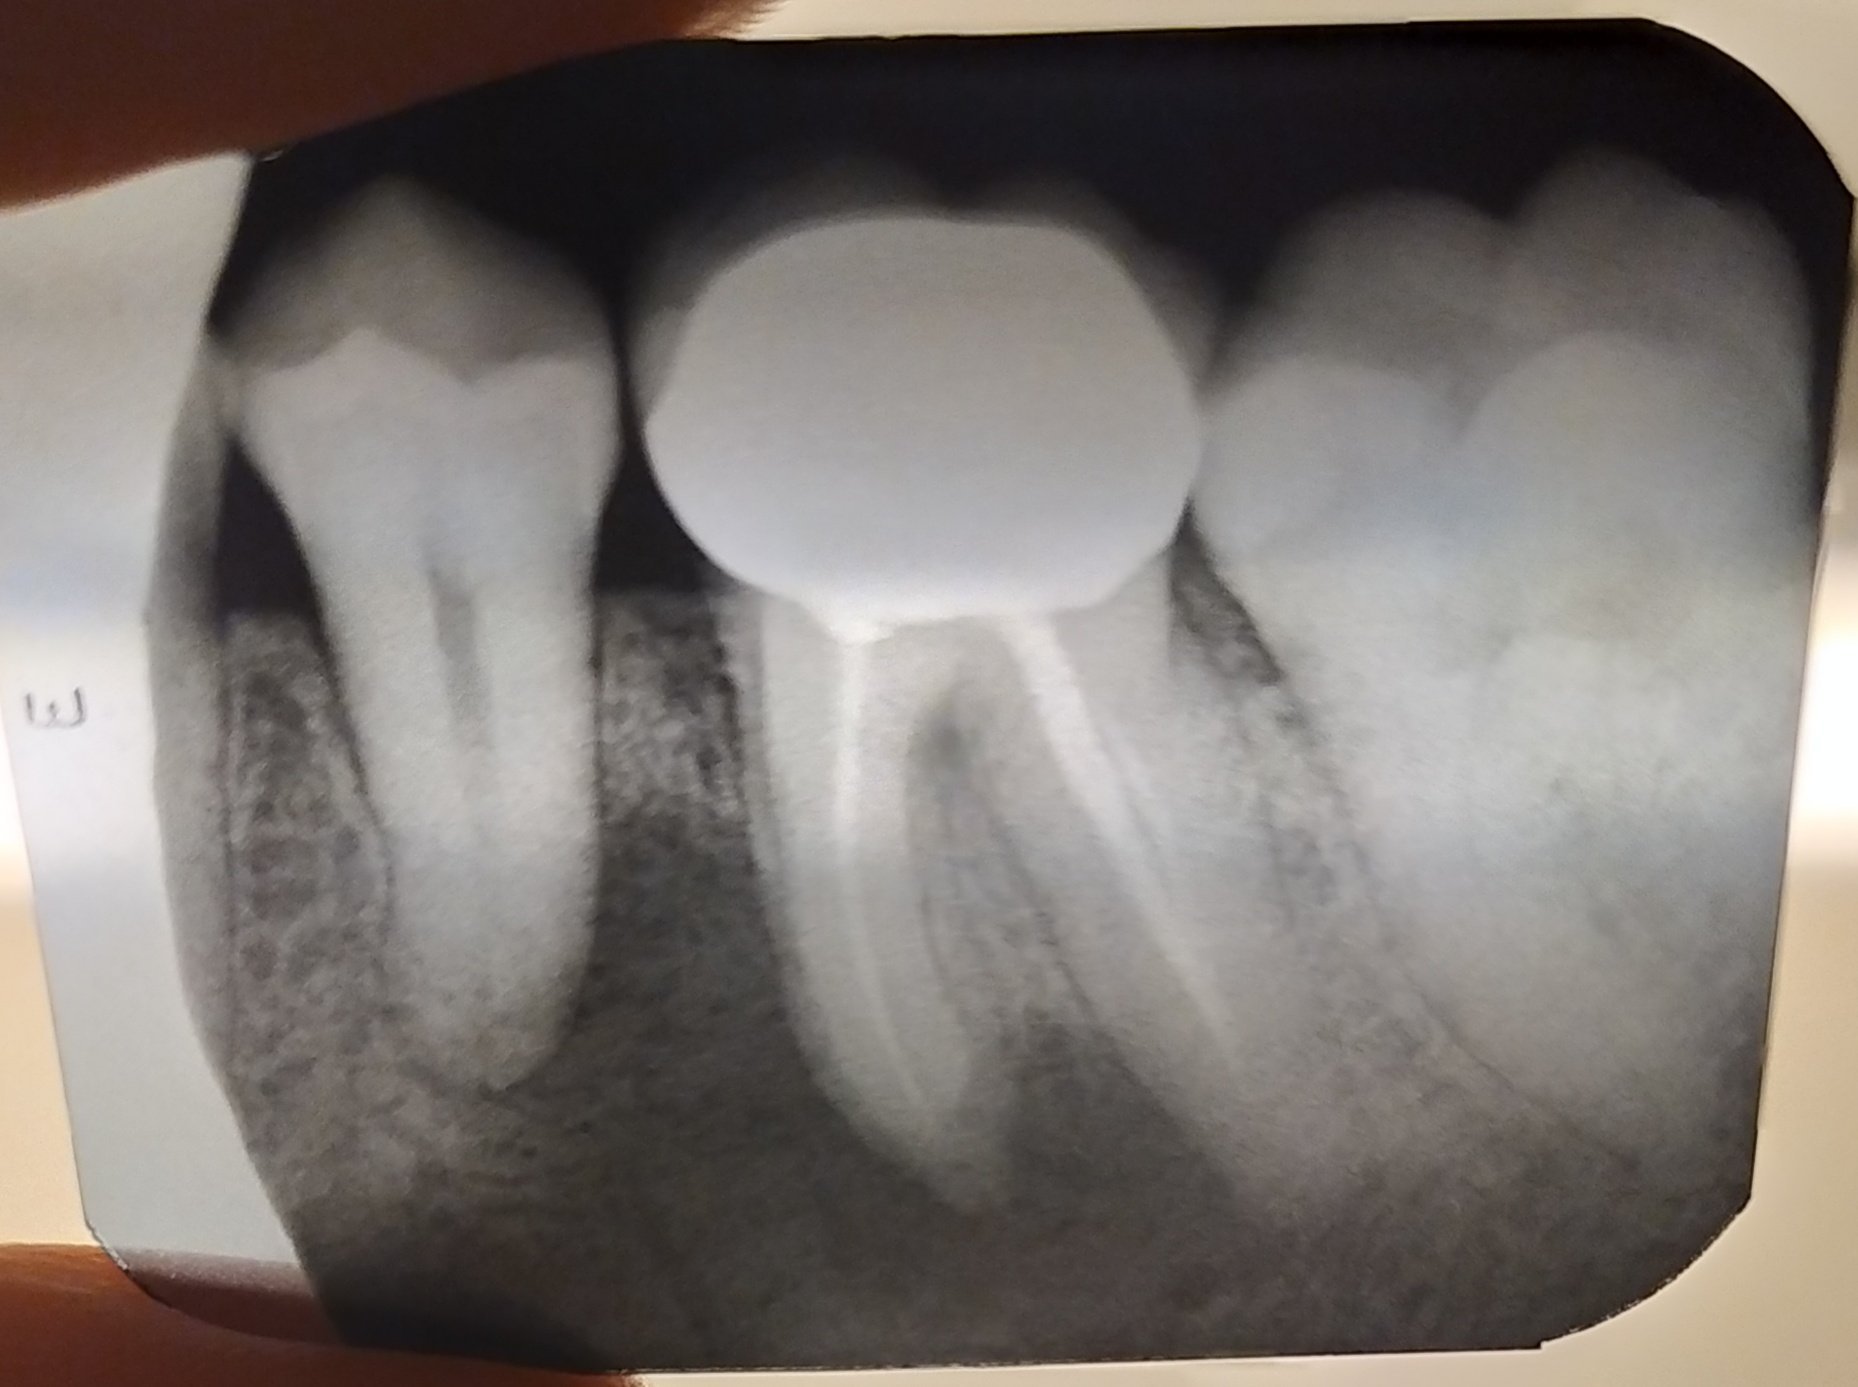

Какво се случва с кореновия канал, ако пълнежът излезе извън него?

Ако пълнежът излезе извън коренови канал, това може да създаде проблеми. Излизането на пълнежа може да доведе до инфекция или реинфекция на зъба. В такъв случай е необходимо да се консултирате със зъболекар, който може да прецени дали е необходимо повторно лечение на кореновите канали или други процедури за спасяване на зъба.